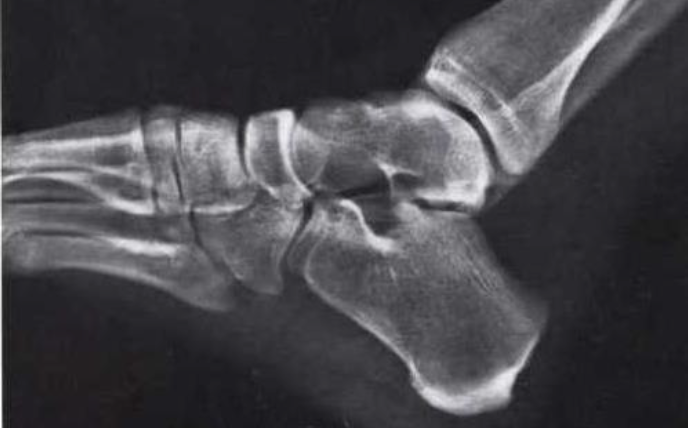

What is this view of the ankle? what views are missing?

Oblique

MISSING:

AP

Lateral